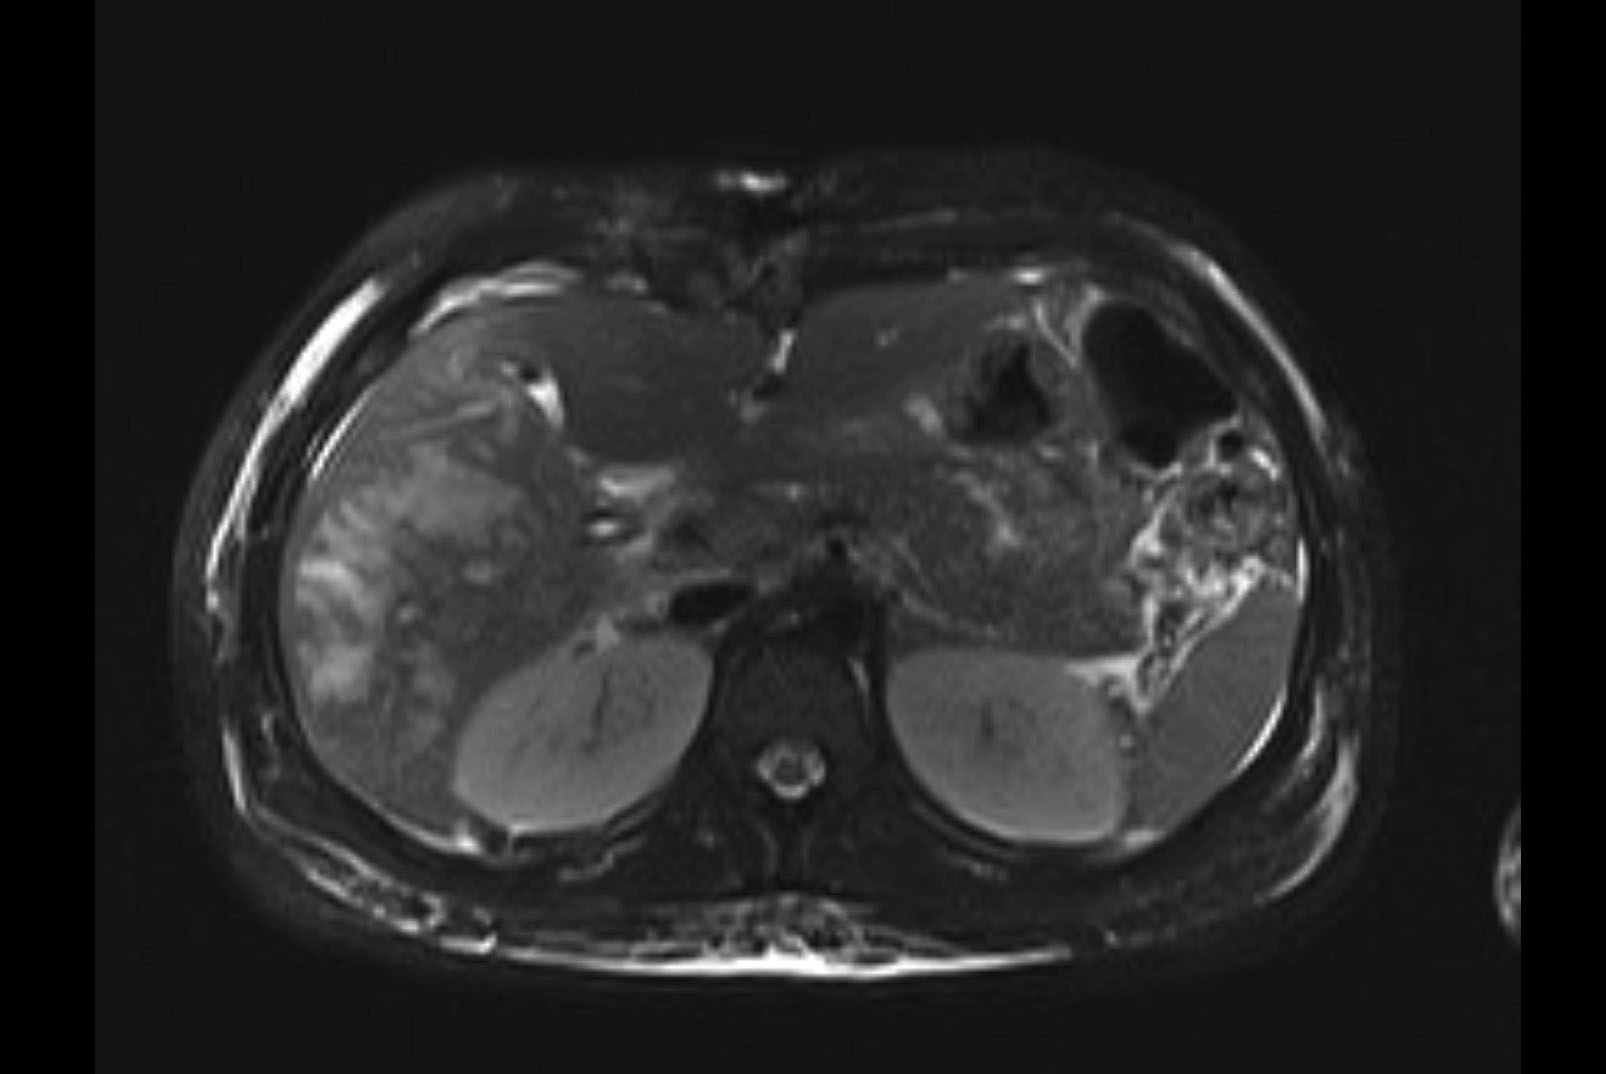

MRI T2